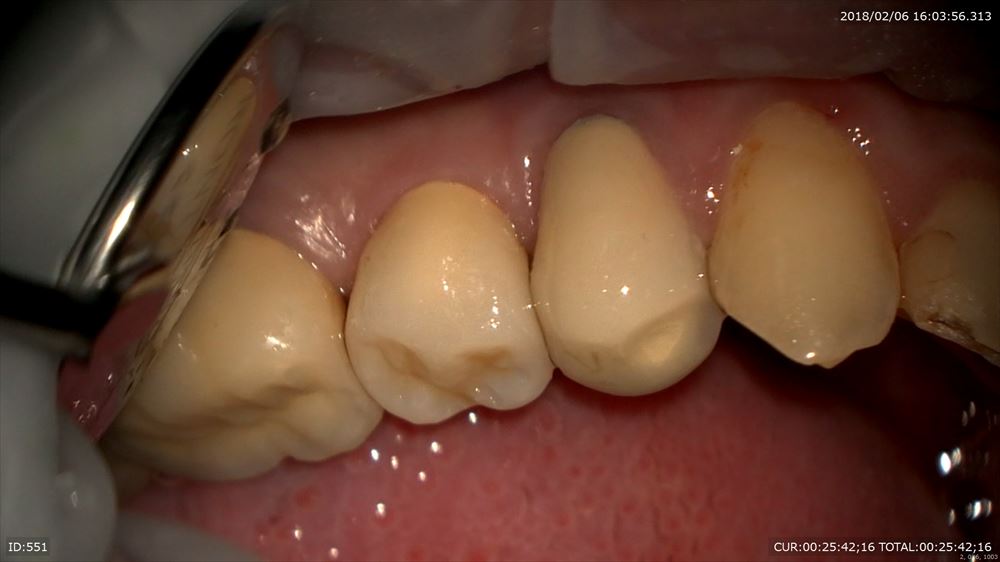

次のケースはハイブリットのセット

これは仮歯。仮歯入れない事はありません。歯茎の為。かみ合わせの為必須。

仮歯を外して

セット。喜んで頂けました。元々この方は中等度の歯周病でした。とても真面目に治療に参加して頂き歯周病の再発はありません。本当に感謝。次回PMTC!